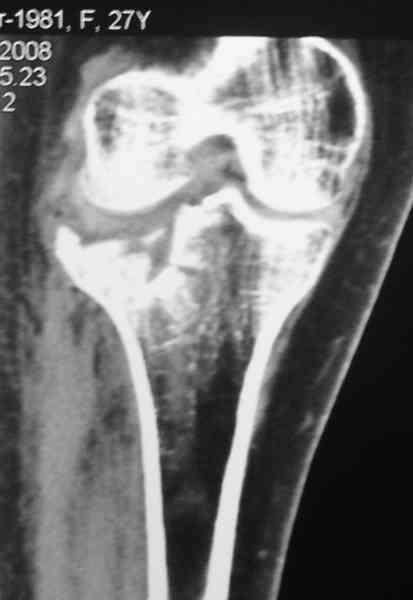

[Ortho] Застарелый перелом 41С3

Уважаемый Абдурашид. Если нет противопоказаний , то из оперативных

способов, я бы рекомендовал следующие: Полное замещение наружного

мыщелка аллотрансплантатом либо открытая репозиция с элевацией и

замещение дефекта ауто или аллокостью. В Ваших условиях , я бы

рекомендовал второй способ. Во-время элевации необходимо разъединить

фрагменты со стороны сустава ( надсечь скальпелем по линиям перелома,

а затем тонким остеотомом их разъединить. При помощи долота произвести

неполную остеотомию ( захватите не менее 1,5 - 2 см губчатой кости и

поднять фрагменты, визуально отрепонировать и фиксировать 2-3 спицами.

Дефект заместить костным ауто или аллотрансплантатом. Окончательная

стабилизация пластиной ( лучше с угловой стабильностью, либо АВФ -

позволит спокойно устранить угловую деформацию.

Недавно поступила больная через 1,5- 2 месяца.